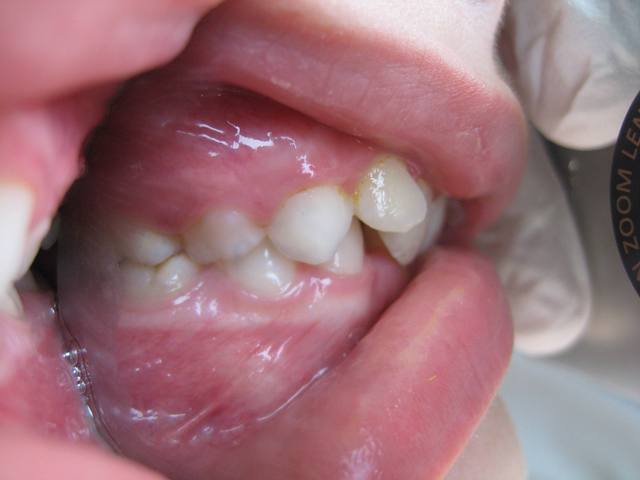

Photos endobuccales  2  wxrxfq - Eugenol

Elle présente une linguo-version et une égression des incisives maxillaires et mandibulaires. Le truc c'est que les racines de 11 et 21 semblent bien positonnées sur la télé de profil, alors que les faces vestibulaires sont très lingualées.

C'est une Cl II/2 non ?

je crois que la forme très bombée de la couronne de centrale sur la radio, et qu'on ne voit pas sur les photos, est due à la superposition des quartes inciives. Quand au traitement, il s'agit d'un traitement classique d'un cas de classeII div 2.

Jeamba, je me demandais que faire uniquement par rapport à l'angulation entre les axes radiculaire et coronaire des incisives. Pour le reste j'ai vu que c’était une classe II2